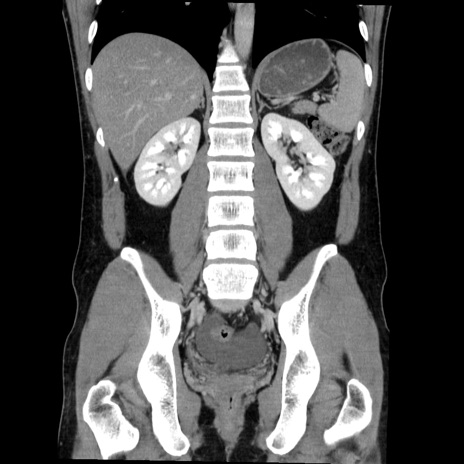

症例36(冠状断像)

【症例】20歳代 男性

【主訴】心窩部痛

【現病歴】今朝より上腹部痛あり。一旦軽快していたが再度出現したため救急要請。昨日夕に白身の魚を含む刺身を食べた。

【身体所見】BP 136/89mmHg、HR 74/min、BT 37.0℃、腹部:膨満、軟、心窩部に圧痛あり。反跳痛なし、筋性防御なし、腸雑音やや亢進あり。

【データ】WBC 17700、CRP 0.48